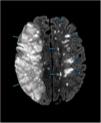

Vasculitis primaria del sistema nervioso central. Una enfermedad rara con alta mortalidad

Primary central nervous system vasculitis. A rare disease with high mortality